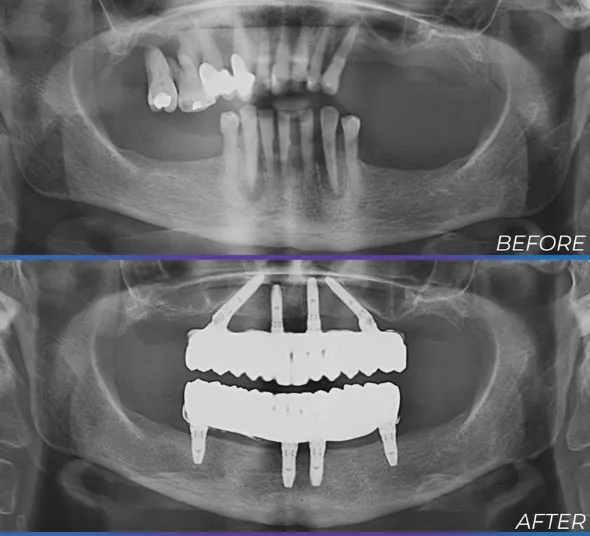

Doamna M.C. s-a prezentat la consultație cu o afecțiune parodontală severă, ireversibilă, care și-a pus amprenta asupra calității vieții sale atât pe plan personal, cât și în relațiile cu cei dragi.

Prin Sistemul de implanturi All-on-4® - soluția care face posibile transformările spectaculoase, doamna M.C. a părăsit cabinetul cu zâmbetul pe buze încă din ziua intervenției chirurgicale, în mai puțin de 24h!